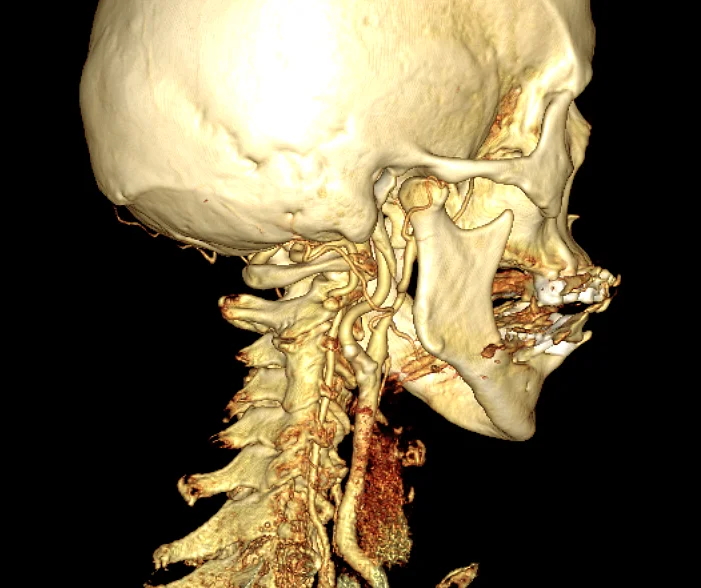

Computertomographie: Gesamtes Spektrum der CT Diagnostik

- CT des Schädels, CT Perfusion des Gehirns

Für die CT-Diagnostik verfügt die Abteilung für Radiologie über zwei moderne Multislice Computertomographen. Es werden Spezialuntersuchungen wie die Herz-CT, Perfusions-CT oder virtuelle CT Kolonographie durchgeführt (siehe Leistungsspektrum).